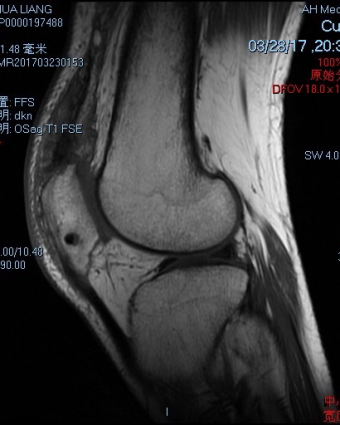

日前,我院运动创伤与关节镜外科针对一例肾移植术后股四头肌腱断裂患者,采取了双侧股四头肌近端重排,股四头肌腱止点重建及自体肌腱加强固定的个性化手术治疗。

患者,男性,35岁,半年前因双肾尿毒症行右侧肾移植手术,围术期发生双侧股四头肌腱病理性断裂,无法站立步行给患者正常生活造成极大不便,但因为手术风险极大,近半年来患者就诊多家医院未果,近日患者就诊于运动创伤与关节镜外科。

股四头肌腱是重要的伸膝装置,断裂后患者无法步行及站立,生活质量受到严重影响,传统股四头肌腱重建需使用大量内植物。徐洪港副主任医师针对该患者特殊体质,与相关科室沟通、会诊及全面的手术方案制备完成后对该患者进行了个性化手术治疗。术中针对患者的特殊情况,不用内植物,而进行骨隧道的方式进行股四头肌腱止点重建,但因患者受伤时间较久,肌腱近端回缩严重,故另取自体半腱肌一根行穿髌骨横向骨隧道进行股四头肌的加强缝合;因左膝肌腱回缩较重,另行了股四头肌肌腱的“Z”形延长术。手术顺利,术中出血不足20ml,术后患者生命体征平稳,已可直腿抬高。